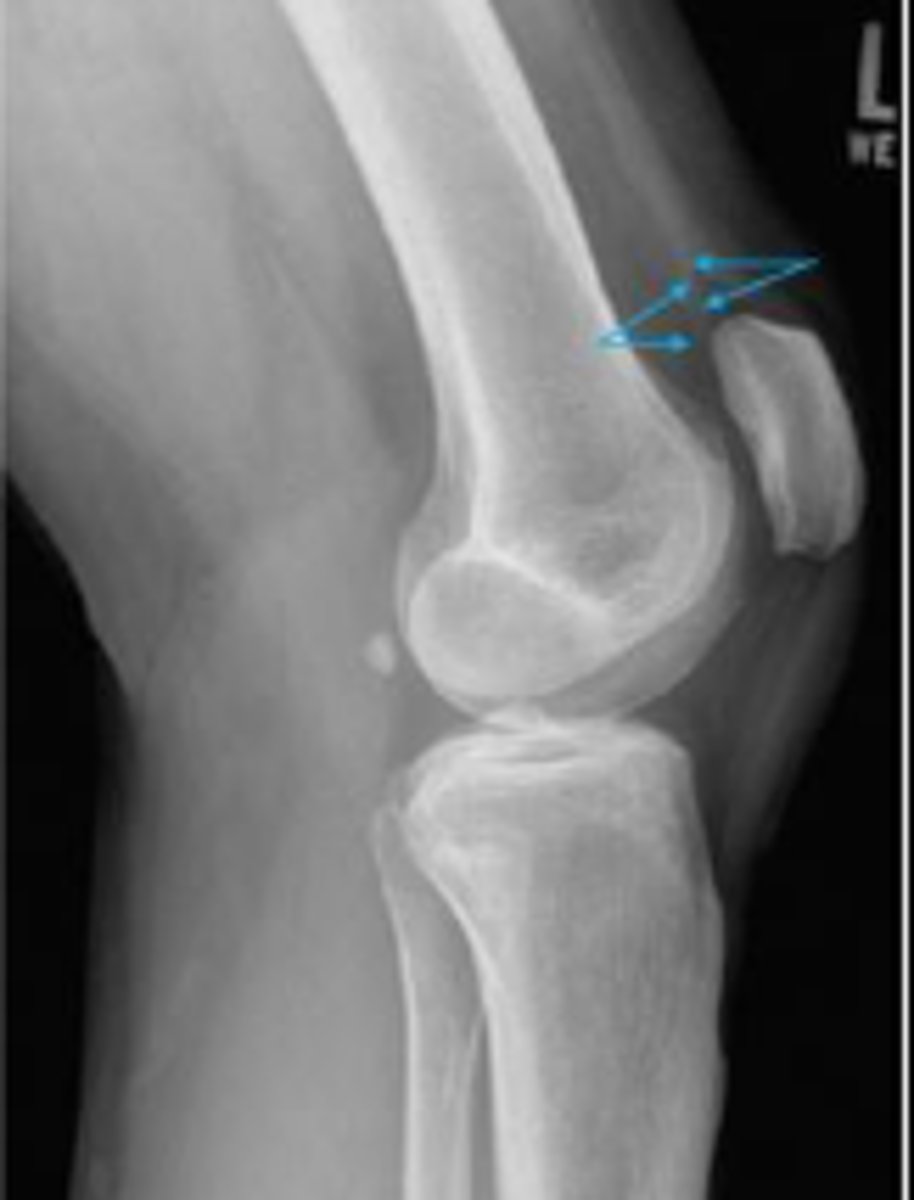

Lateral collateral ligament

What inserts at the location of the blue arrows?

Lateral collateral ligament avulsion fracture of

the right knee

What is the most significant radiographic finding?